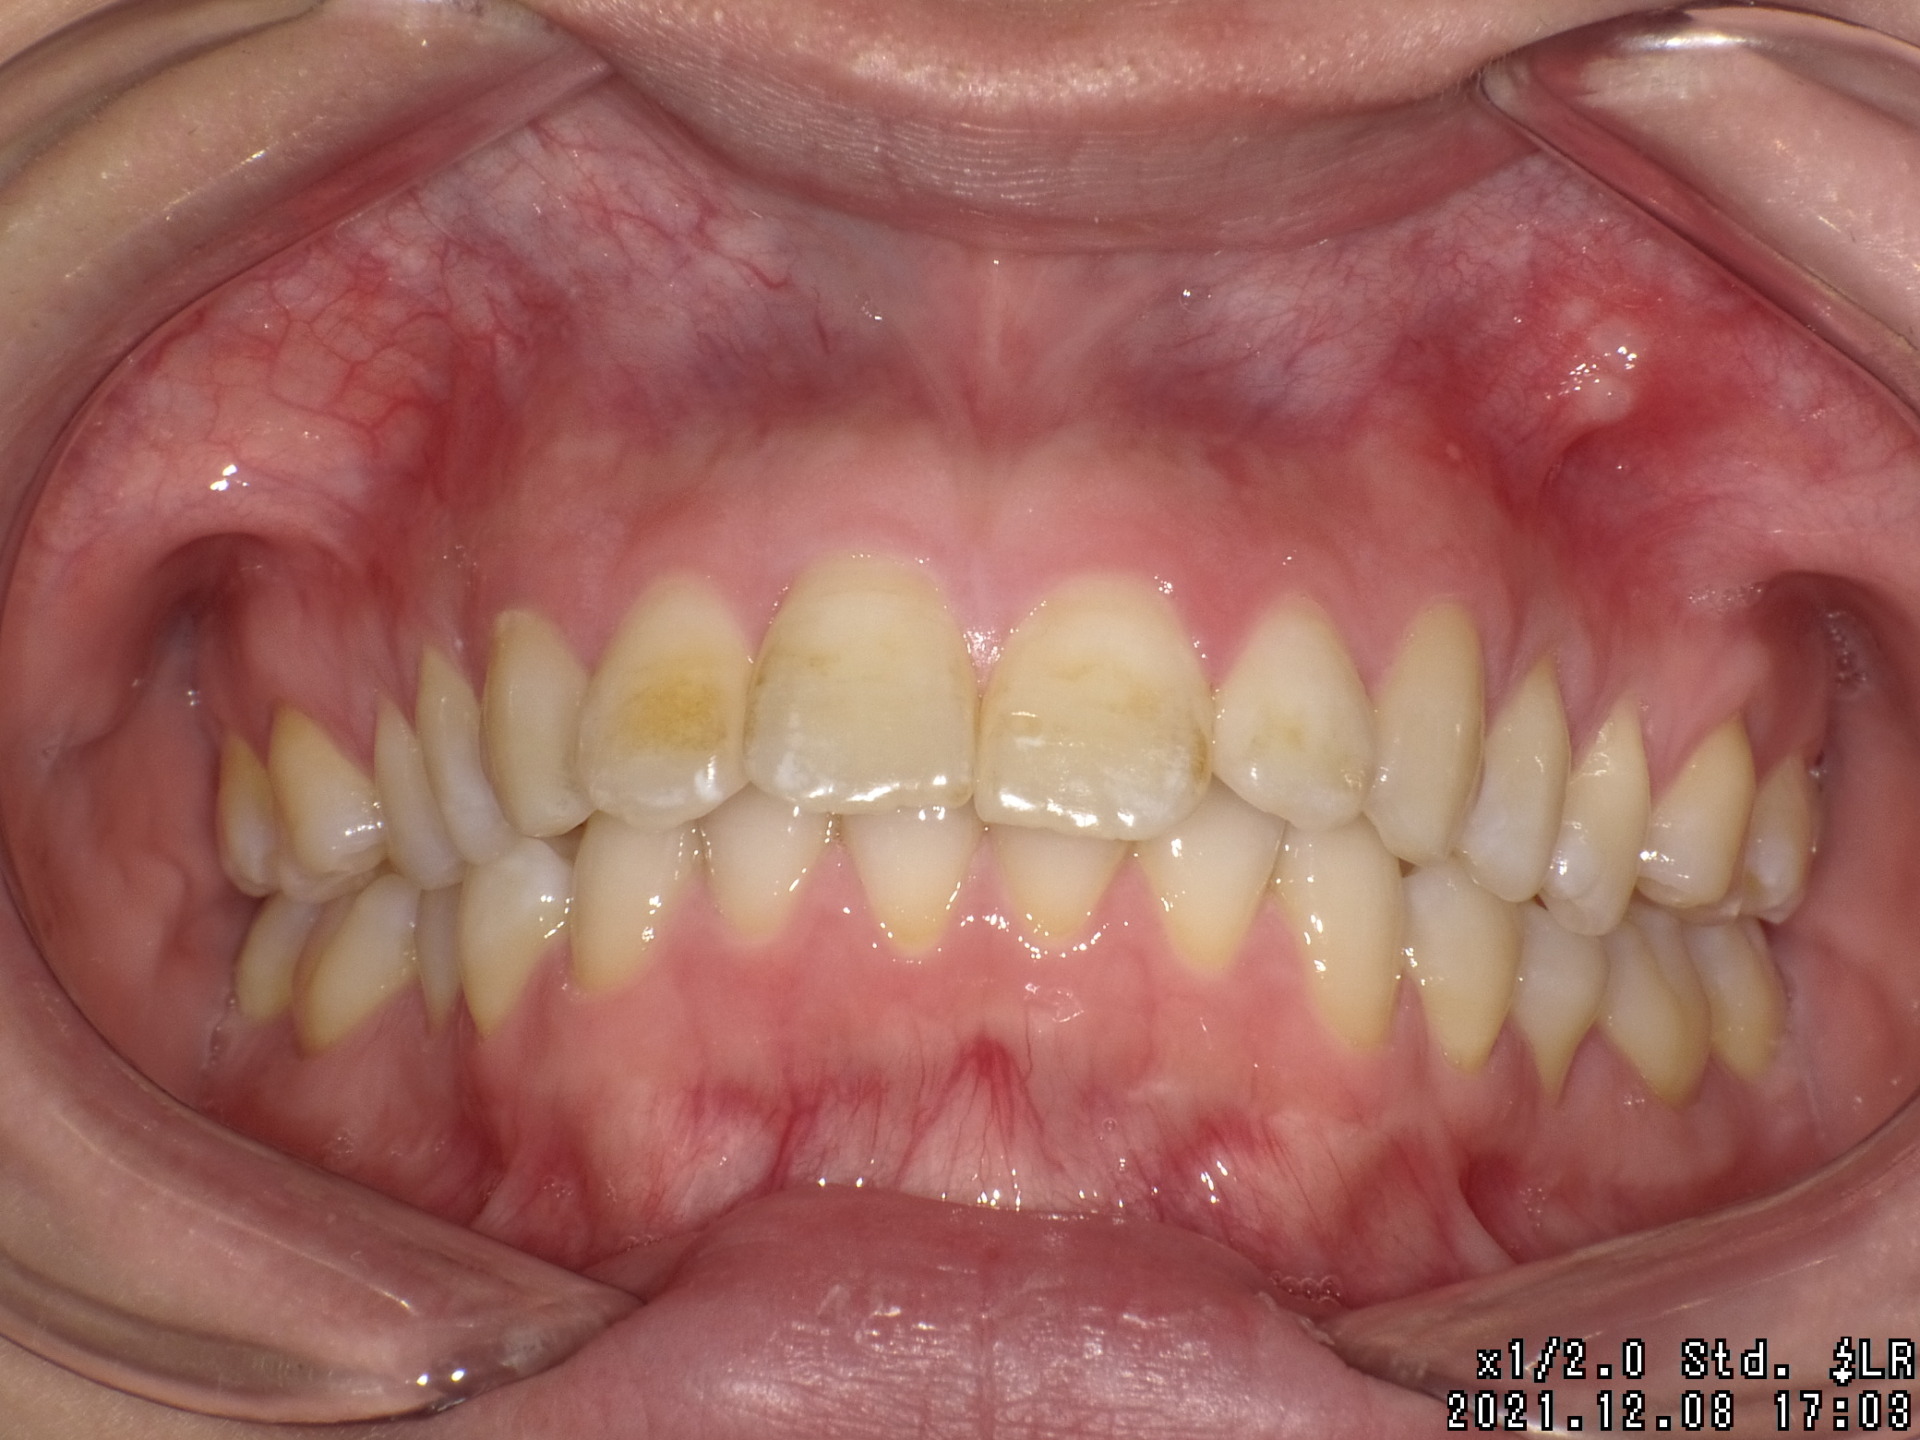

Before

| 症状 | 前歯が出ている |

| 通院目的 | 永久歯を抜かずに歯並びを治したい。 |

| 処置内容 | ディスタライザー・マルチブラケット装置 |

| デメリット・院長コメント | 永久歯を抜かない治療のデメリットは、治療期間が長いことです。 ただし、その後の人生の長さを考えると、健全な小臼歯を2本または4本抜歯の矯正治療よりも、はるかにメリットがあるといえます。 また、アーチが小さくならないので、舌が後ろに押し込まれないためいびき防止につながり睡眠の質の向上にもつながります。 |